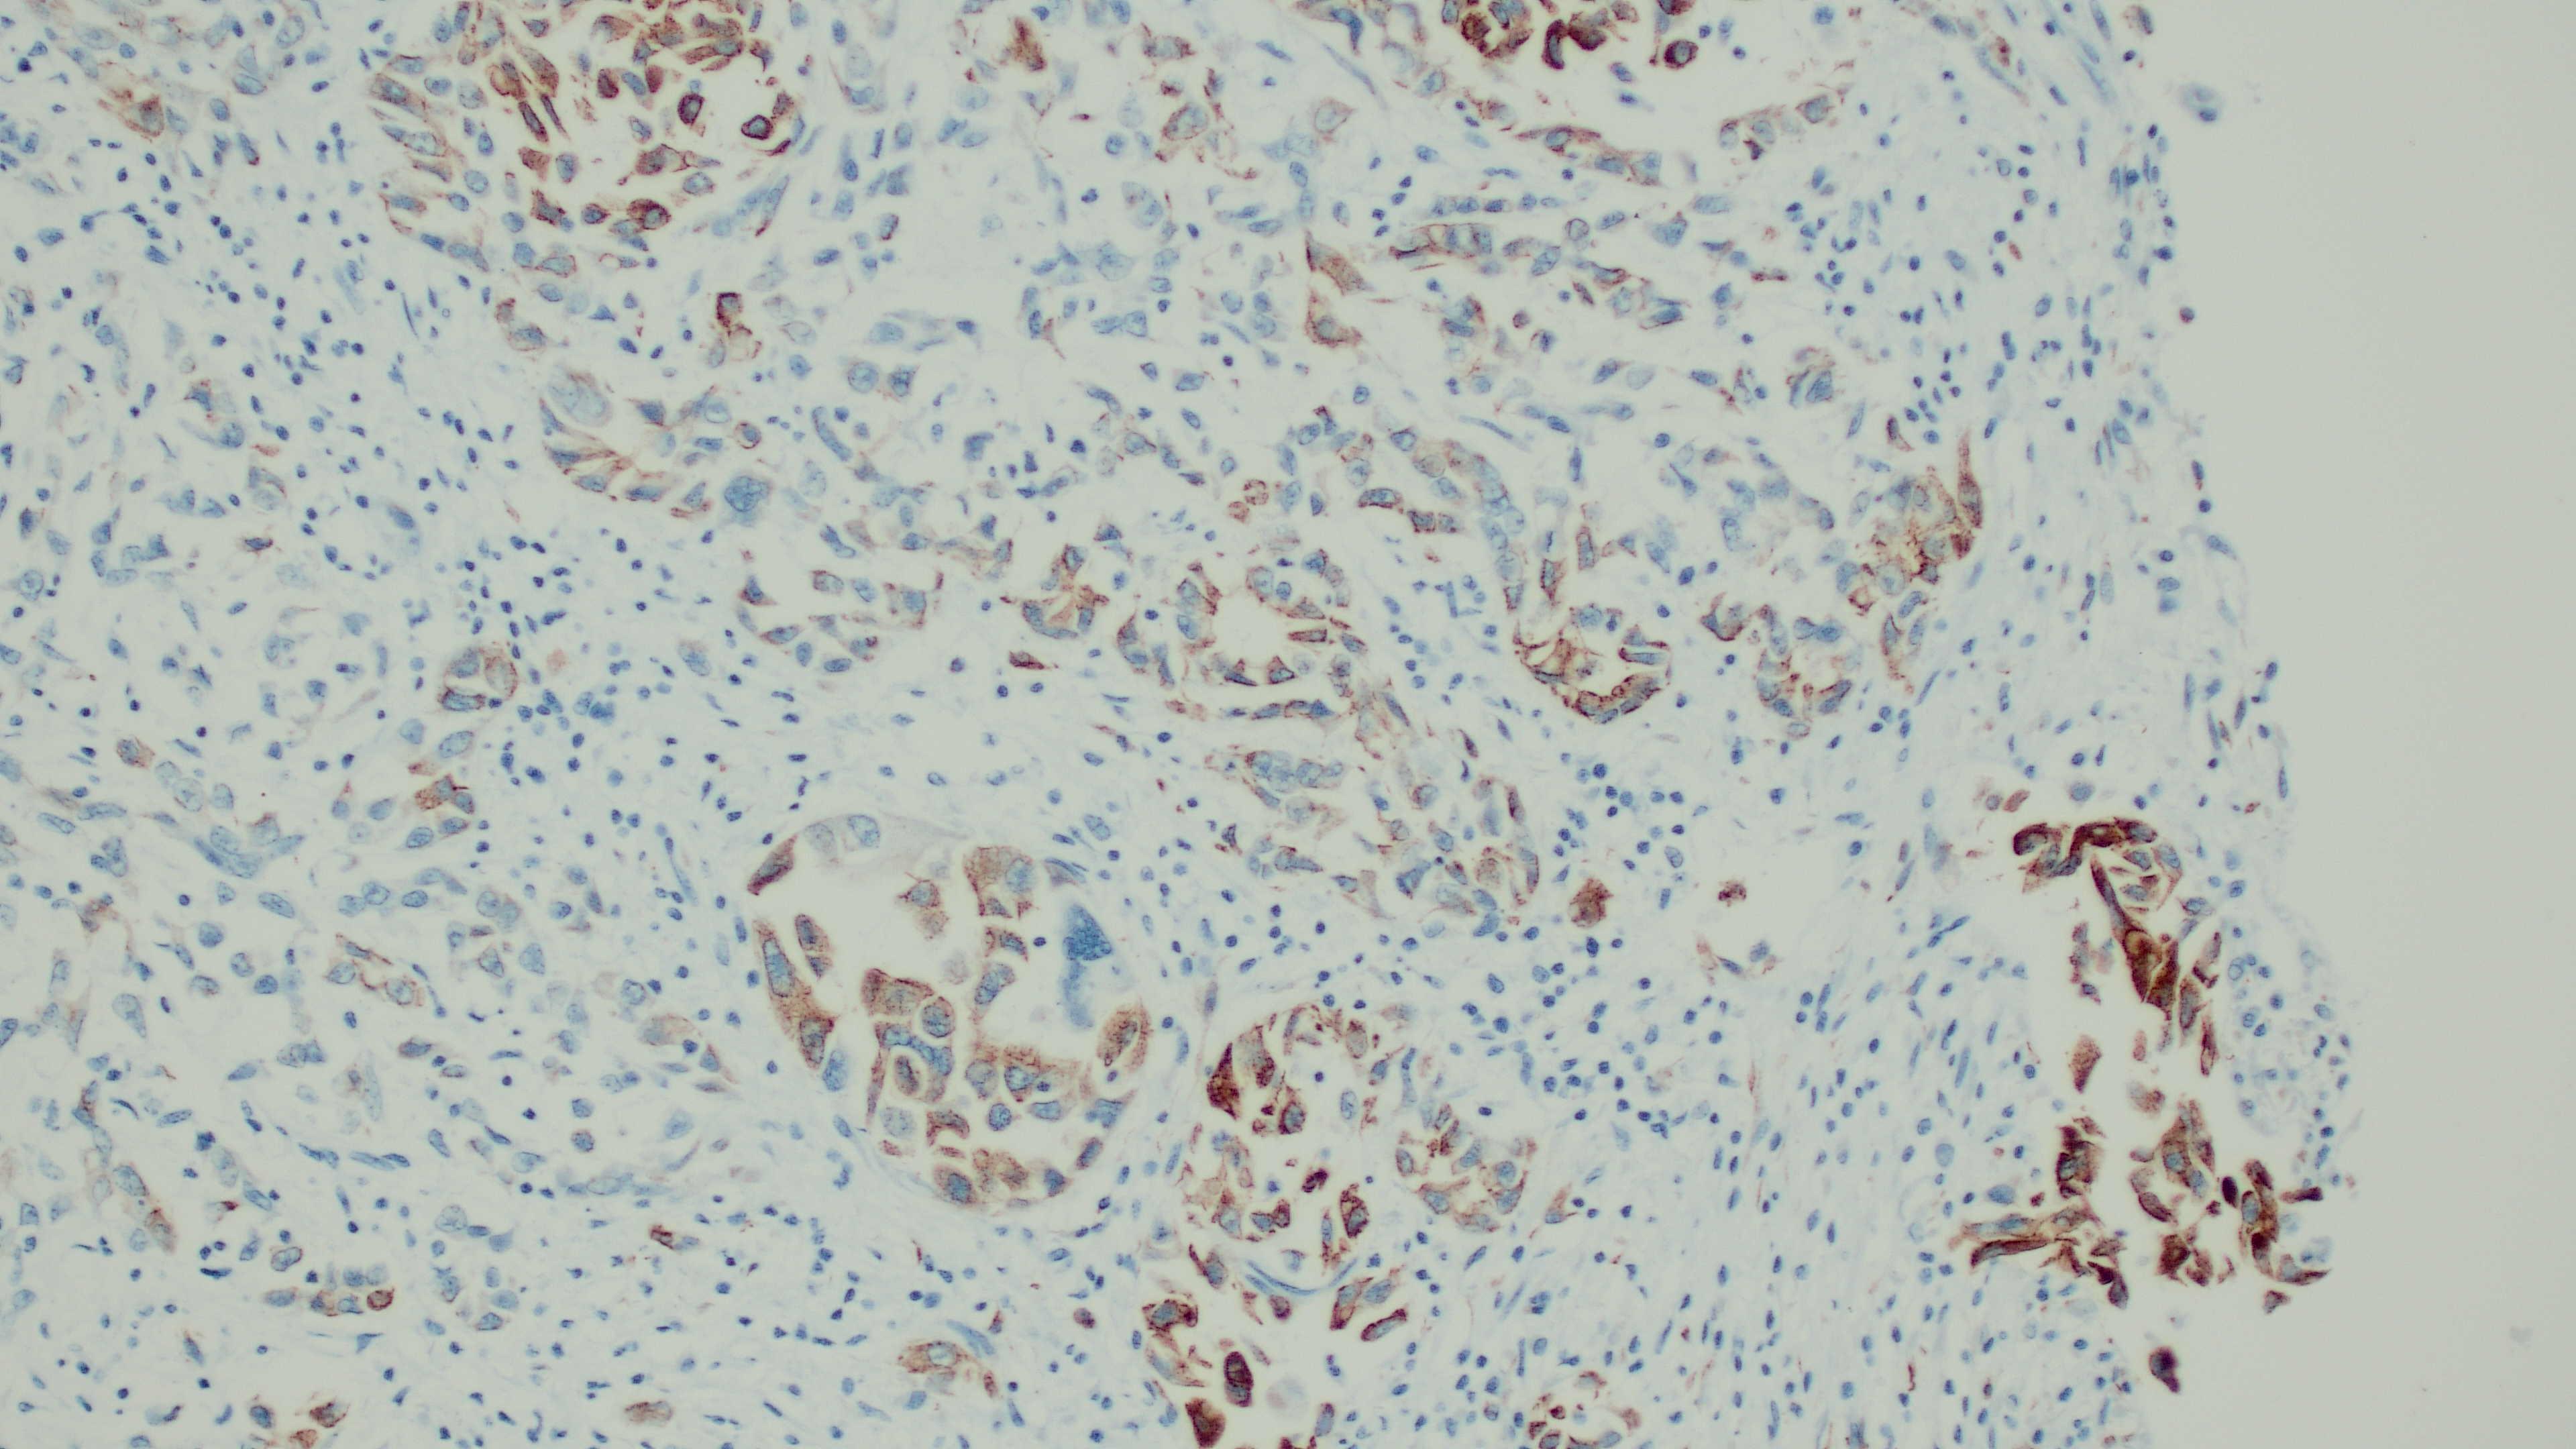

Immunohistochemistry: Neoplastic cells are diffusely strongly positive for vimentin. The majority of neoplastic cells are moderately positive for cytokeratin.

Postmortem examination revealed the presence of a neoplastic process within the pleural and peritoneal cavity, which on histopathology had a morphology most likely consistent with a mesothelioma.3,12 Additionally, the immunopositivity of both cytokeratin and vimentin, is consistent with a mesothelial origin, although rarely this dual positivity can be present in metastatic ovarian or renal carcinomas, which were not identified in this case.12

Stromal invasion usually apparent (highlight with pancytokeratin staining) |

Expansile nodules; disorganized growth (highlighted on cytokeratin staining) |

While this immunohistochemistry (IHC) profile can be a useful feature for diagnosis, there are other neoplasms that can express dual positivity for pancytokeratin and vimentin when neoplastic cells undergo EMT. As mentioned by the contributor, this has been reported in metastases from both ovarian and renal carcinomas.16 It has also been documented in melanomas and aggressive metaplastic mammary carcinomas in humans.9 The absence of an additional primary neoplasm can help rule out other tumors, but there are other IHCs utilized in veterinary literature to assist in definitively diagnosing mesotheliomas. The JPC performed in-house calretinin and Wilms Tumor 1 (WT1) immunohistochemistry on this case post-conference, as both of these markers have been utilized in animal species to diagnose mesothelioma successfully.20 Unfortunately, neither of these IHCs worked on the donkey tissue in this case.